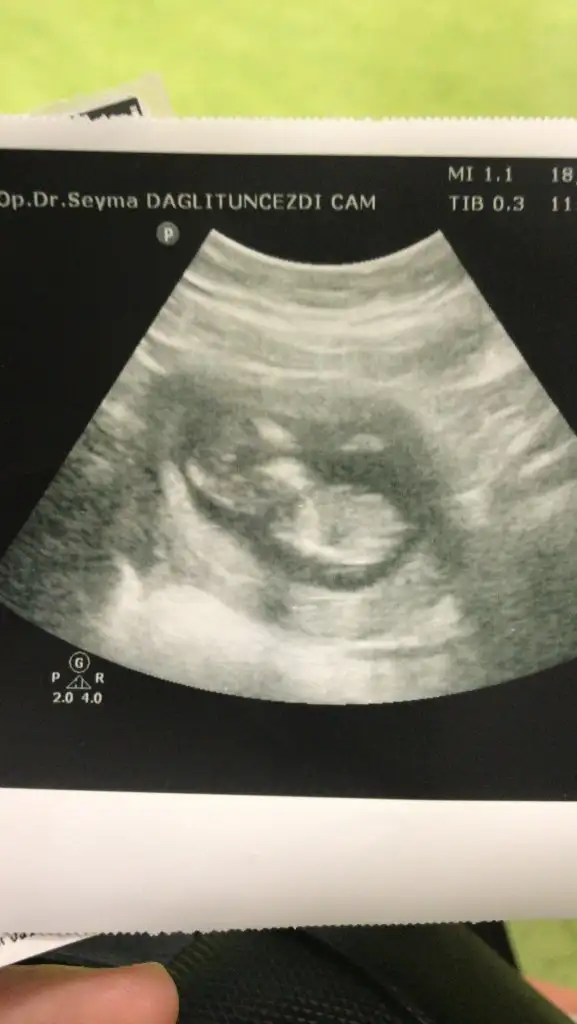

Kız sanki emin olamadımBana da tahminde bulunur musunuz 11 haftalık![]()

12.hafta burdaKız sanki emin olamadım 12-13 hafta olursa paylaşın

12+2Kız sanki emin olamadım 12-13 hafta olursa paylaşın